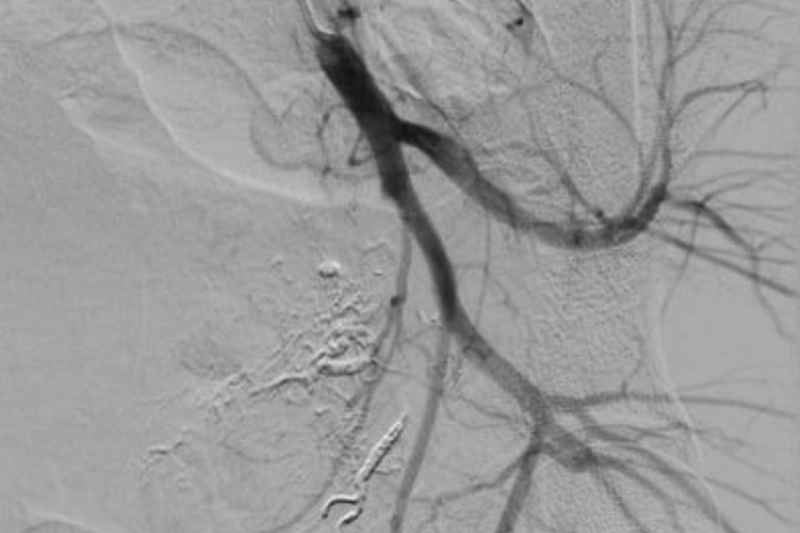

Hình ảnh thoát thuốc vị trí động mạch tử cung trái và quanh trực tràng của bệnh nhân (Ảnh - BVCC) |

Nhớ lại khoảnh khắc “đấu trí” với tử thần, BSCKII. Phan Hoàng Giang - người trực tiếp thực hiện ca can thiệp - cho biết: “Đây là lần đầu tiên, tôi gặp trường hợp chảy máu sau đẻ mà nguồn gốc lại từ động mạch mạc treo tràng dưới. Ca lâm sàng này rất hiếm gặp trên thế giới. Ca lần đầu tiên được phát hiện là vào năm 2015. Trong một nghiên cứu lên đến 783 bệnh nhân thì chỉ có 8 bệnh nhân mắc (chiếm 1% các trường hợp chảy máu sau đẻ). Với những bệnh nhân đã cắt tử cung càng khó khăn trong quá trình tìm động mạch tử cung nhằm cầm máu và gây tắc. Ca sản phụ này khá phức tạp và mất nhiều thời gian hơn so với ca chảy máu sau đẻ thông thường. Bình thường, chúng tôi chỉ gây tắc nhánh mạch tổn thương và cầm máu tạm thời động mạch chậu trong hai bên”.

Với bệnh nhân này, các bác sĩ đã tìm thêm các nhánh chảy máu quanh trực tràng, gồm 6 nhánh mạch 2 bên: động mạch trực tràng trên, động mạch trực tràng giữa và động mạch trực tràng dưới. Sau khi xác định được nhánh chảy máu, các bác sĩ đã lựa chọn vật liệu gây tắc mạch cũng như vị trí can thiệp để không bị hoại tử trực tràng. Sau 36 tiếng theo dõi, sản phụ đã được xuất viện, trở về nhà cùng chồng và 3 con nhỏ.